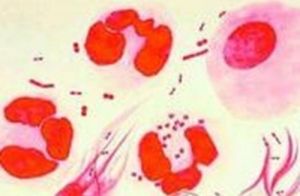

2.形態與染色淋球菌呈卵圓形或豆形,菌體長0.6~0.8µm,寬約0.5µm。常成對排列,鄰近面扁平或稍凹陷,像兩粒豆子對在一起。無鞭毛,不形成芽孢。在急性感染的機體內,其形態較典型,多位於細胞漿內。慢性期則在細胞外。淋球菌革蘭染色陰性。用鹼性美藍染色時,菌體呈藍色。用Pappehheim Saathof染色時,菌體呈紅色,背景為天藍色,十分清晰。 淋球菌在人工培養基上有五種不同的菌落形態,分別稱為T1,T2,T3,T4,T5,其中T1和T2有毒力,T3和T4無菌毛,不能感染人類。